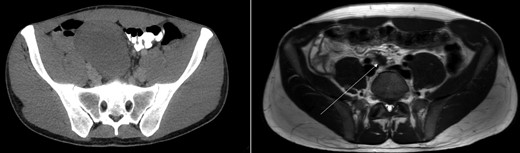

Coronal view of CT-abdomen (left) and MRI-abdomen 1 year later. The lesion has regressed significantly (arrow).

Sonography after three months showed a reduction in size to 9.4 × 5.4 cm2. On request of the patient, who was anxious of having a tumor which was treated conservatively, a second opinion was performed at an University Medical Center. They acknowledged the conservative approach and advised follow up with magnetic resonance imaging (MRI) 1 year after diagnosis. This MRI showed regression of the tumor with a small residue of 2.2 × 1.2 × 1.9 cm2 (Figs 1 and 2) along the right ureter and a minimal hydronephrosis of the right kidney without loss of renal function. A second MRI 6 months later and a third MRI 1 year later showed persisted regression without hydronephrosis. Both scans showed no other masses. The patient did not develop any symptoms during follow up.